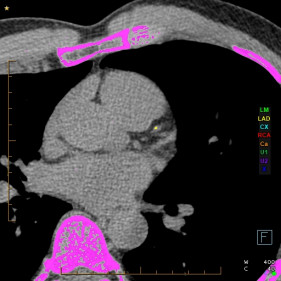

A CT Calcium Score is a quick, non-invasive scan that measures the amount of calcium buildup in your heart’s arteries. This calcium is a sign of atherosclerosis, or hardening of the arteries, which increases your risk of a heart attack.

A CT Calcium Score scan is simple, fast, and does not require any injections or contrast. You will lie on a scanning table, and a low-dose CT scanner will take images of your heart in just a few minutes. The results are then analysed by one of our specialists, and a calcium score is provided. We may also provide you with an adjusted risk of a coronary event.

Your calcium score helps determine your level of risk:

• 0             Very low risk (no coronary calcium)

• 1 - 100       Low risk (mild plaque build-up)

• 101 - 400  Moderate risk (significant plaque build-up)

• >400       High risk (requires further assessment and management)

The higher your score, the higher your risk of a heart attack or other heart-related event.